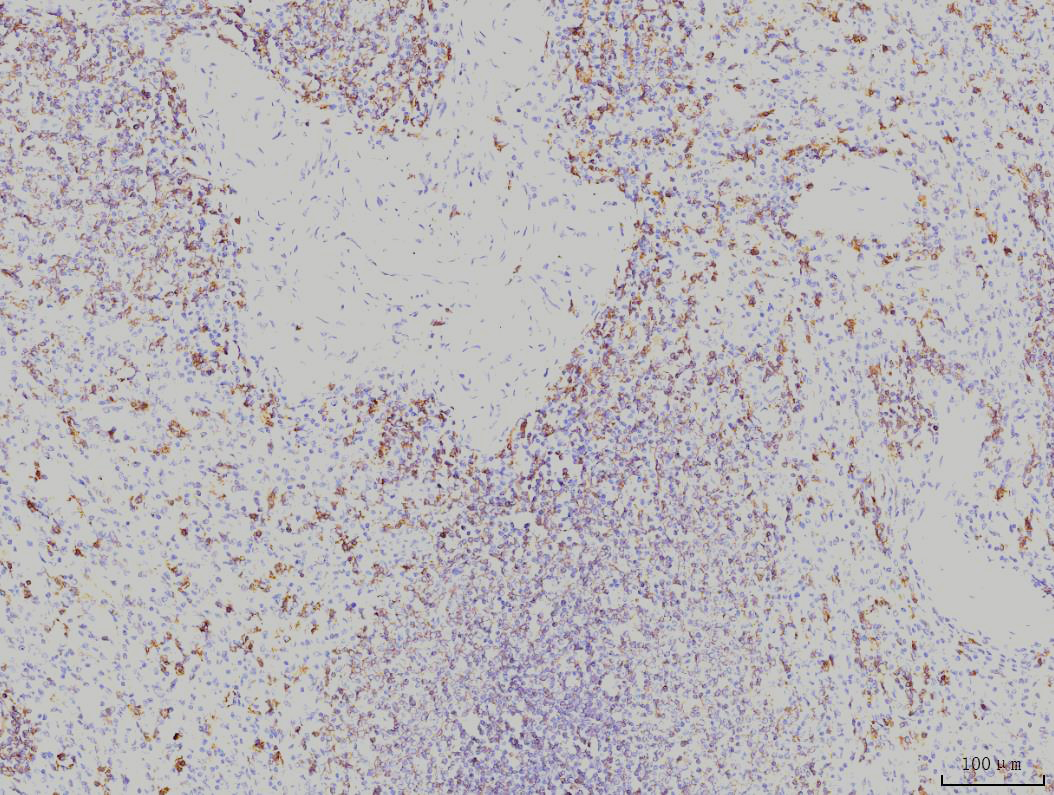

IHC analysis of RAB11A using anti-RAB11A antibody (M01436-2).

RAB11A was detected in a paraffin-embedded section of human spleen tissue. Biotinylated goat anti-mouse IgG was used as secondary antibody. The tissue section was incubated with mouse anti-RAB11A Antibody (M01436-2) at a dilution of 1:200 and developed using Strepavidin-Biotin-Complex (SABC) (Catalog # SA1021) with DAB (Catalog # AR1027) as the chromogen.